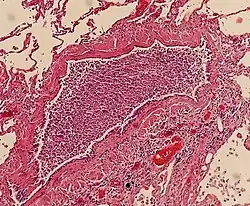

Light microscopy typically shows neutrophils in bronchi, bronchioles and adjacent alveolar spaces.[2]